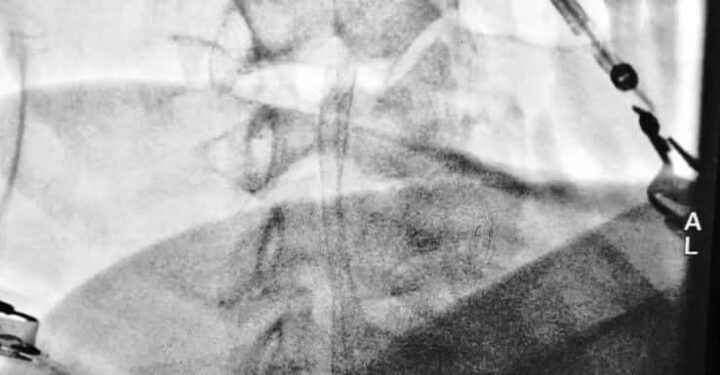

وبينت ادارة المستشفى ان المريض كان يعاني من جلطات دماغية متكررة بسبب إنسداد شبه كامل في الشريان السباتي الأيمن وأجريت له عملية فتح الشريان وزرع شبكة وتكللت العملية بالنجاح والمريض بحالة صحية جيدة بجهود الفريق الطبي والتمريضي والصحي الساند في المستشفى.